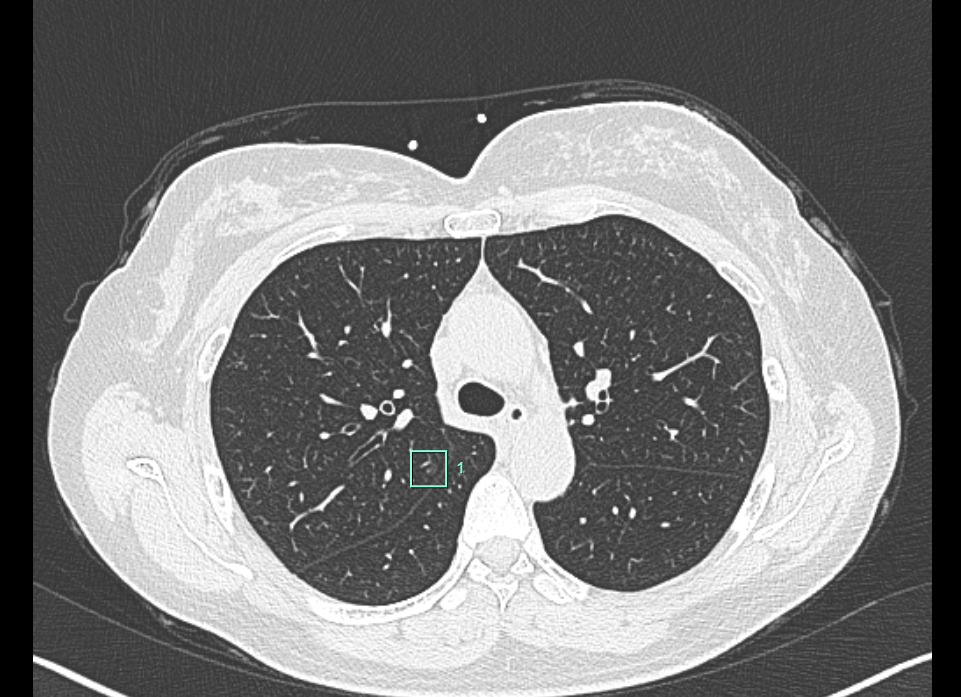

近日,刘女士因胸闷到河南省胸科医院胸外科九病区杜佳辉门诊就诊,胸部CT示右肺上叶后段结节。结节位置很深,普通的定位针很难达到,即使定位成功也会让患者感到疼痛不适。刘女士本身对疼痛耐受程度很低,门诊的时候就多次强调怕疼。

经过讨论,手术由杜佳辉主刀,于海峰担任第一助手,徐家文担任第二助手顺利展开。术前应用磁导航定位,将定位剂准确定位于结节,然后进行荧光镜下右肺上叶后段切除术,手术非常顺利,手术结束当天下午刘女士忍不住就要下床活动,充分体现了胸外科九病区此种新技术极致微创的优势,术后3天刘女士讲述没有感觉到疼痛,像在医院旅了次游,身心压力都得到了治愈。